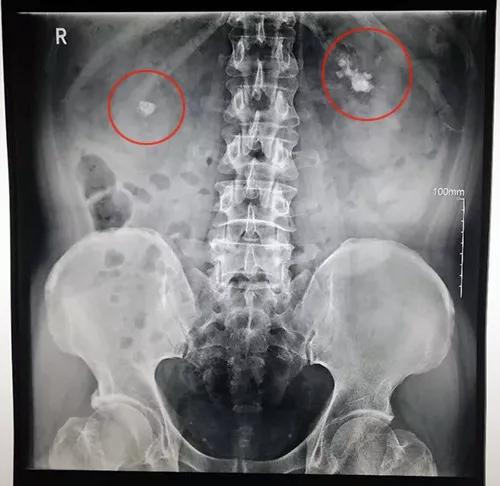

诊断:输尿管结石、双侧输尿管上段结石伴双肾积水、双肾多发结石、2型糖尿病、高血压

泌尿系彩超提示:左肾积水并左侧输尿管上段结石,右肾中度积水并右侧输尿管起始部多发结石,双肾多发结石。

吴先生进行的检查结果,最终诊断结果为:输尿管结石、双侧输尿管上段结石伴双肾积水、双肾多发结石、2型糖尿病、高血压。